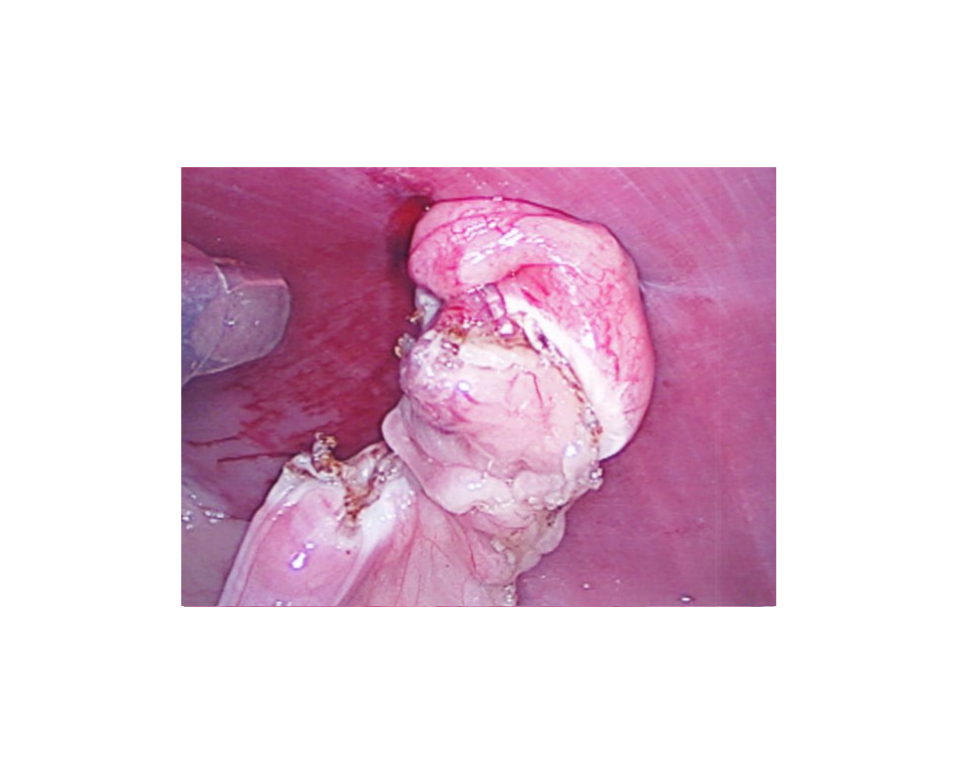

Each ovary is removed through the instrument portal.